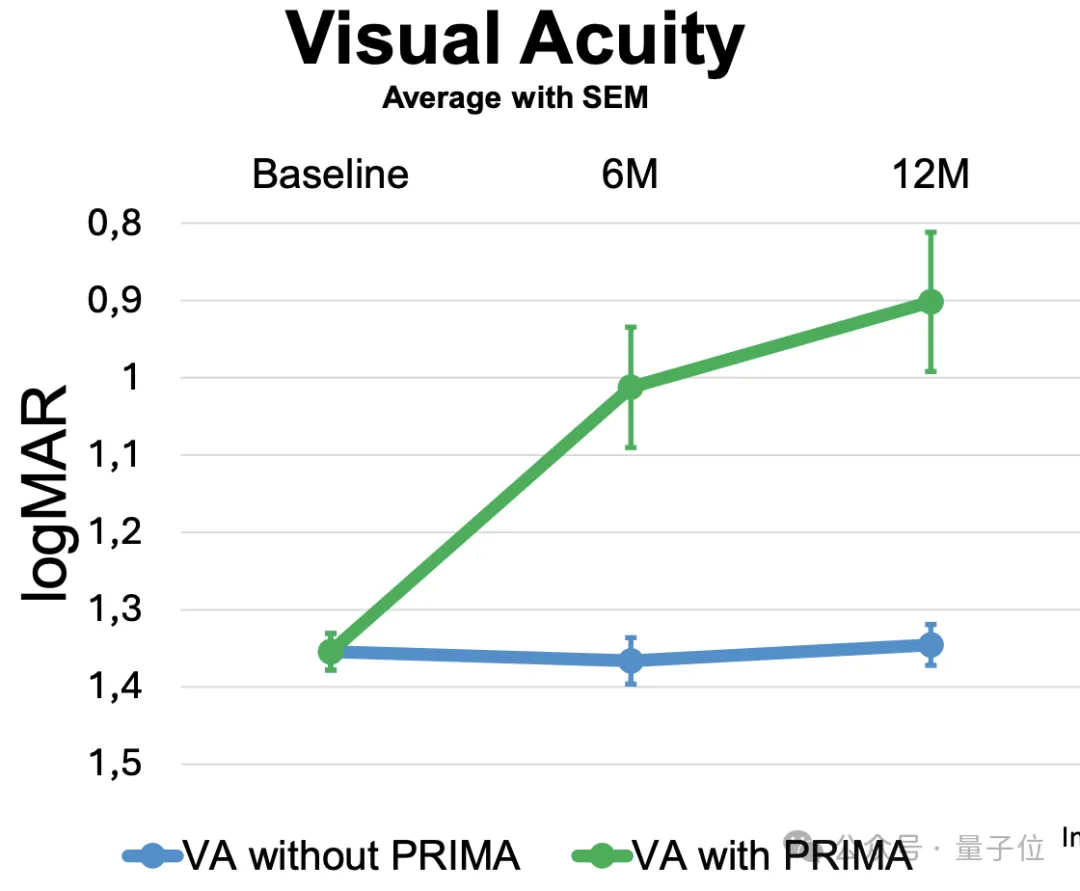

定量上看,研究者在植入后6个月和12个月时,对所有患者的视力通过logMAR评分进行了测量(logMAR为0表示视力正常,正值表示视力不佳),结果显示出了具有临床意义的改善:

而且患者不使用PRIMA时的平均自然视力在植入后保持稳定,说明了PRIMA植入物具有良好的安全性。